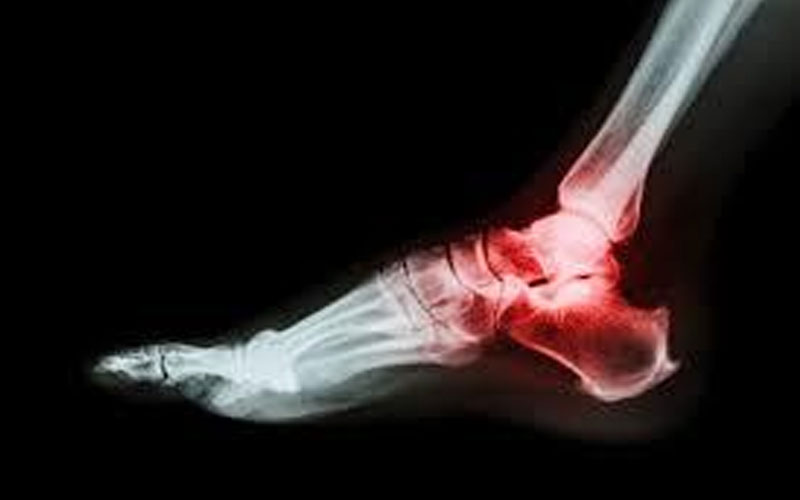

نيسان ـ أكد الدكتور كاسبر جريم أن الكسور الإجهادية (Stress Fractures) عبارة عن شقوق صغيرة في العظام تحدث نتيجة الإجهاد الزائد المتكرر على العظام.

وغالباً ما يحدث الكسر الإجهادي في عظم مشط القدم وعظم الكعب وقصبة الساق والحوض وعنق الفخذ. ويمكن ملاحظته من خلال الشعور بألم في الموضع المصاب وحدوث تورم به وعدم القدرة على التحميل عليه.